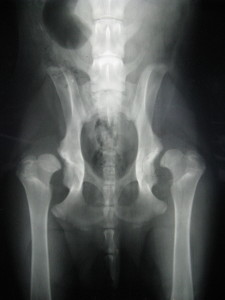

ופה זה ברור שהמפרק אינו במקום.